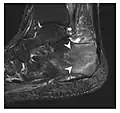

Figure 10: Calcaneal fatigue fracture in a 30-year-old male runner. Radiographs were normal (not shown). (a) Sagittal T1-weighted and (b) short tau inversion recovery images show a linear hypointensity (arrows) of calcaneal tuberosity within diffuse bone marrow edema, which appears as an ill-defined area of hyperintensity on a fluid sensitive pulse sequence (arrowheads).[1]